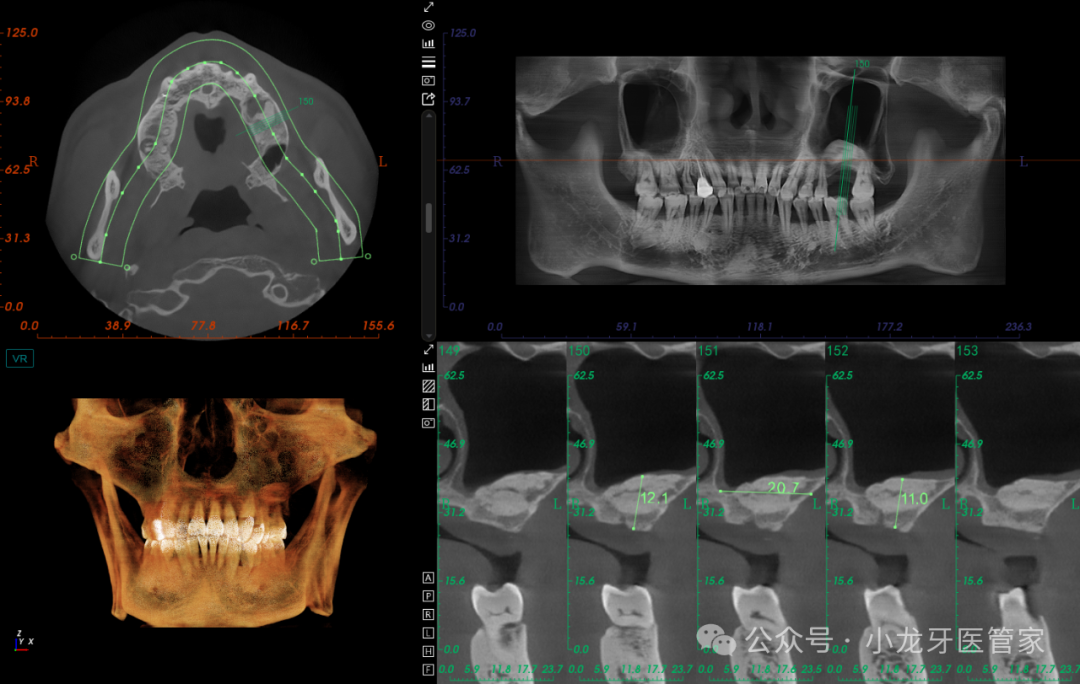

辅助检查:CBCT示左上颌窦较为宽大,窦底剩余骨高度约2mm,窦黏膜厚度约1.5mm,窦腔未见液平面,上颌窦外侧壁骨板完整。

术后6个月影像学图片

(CT上再次的测量数据比之前要理想,成骨效果较好)